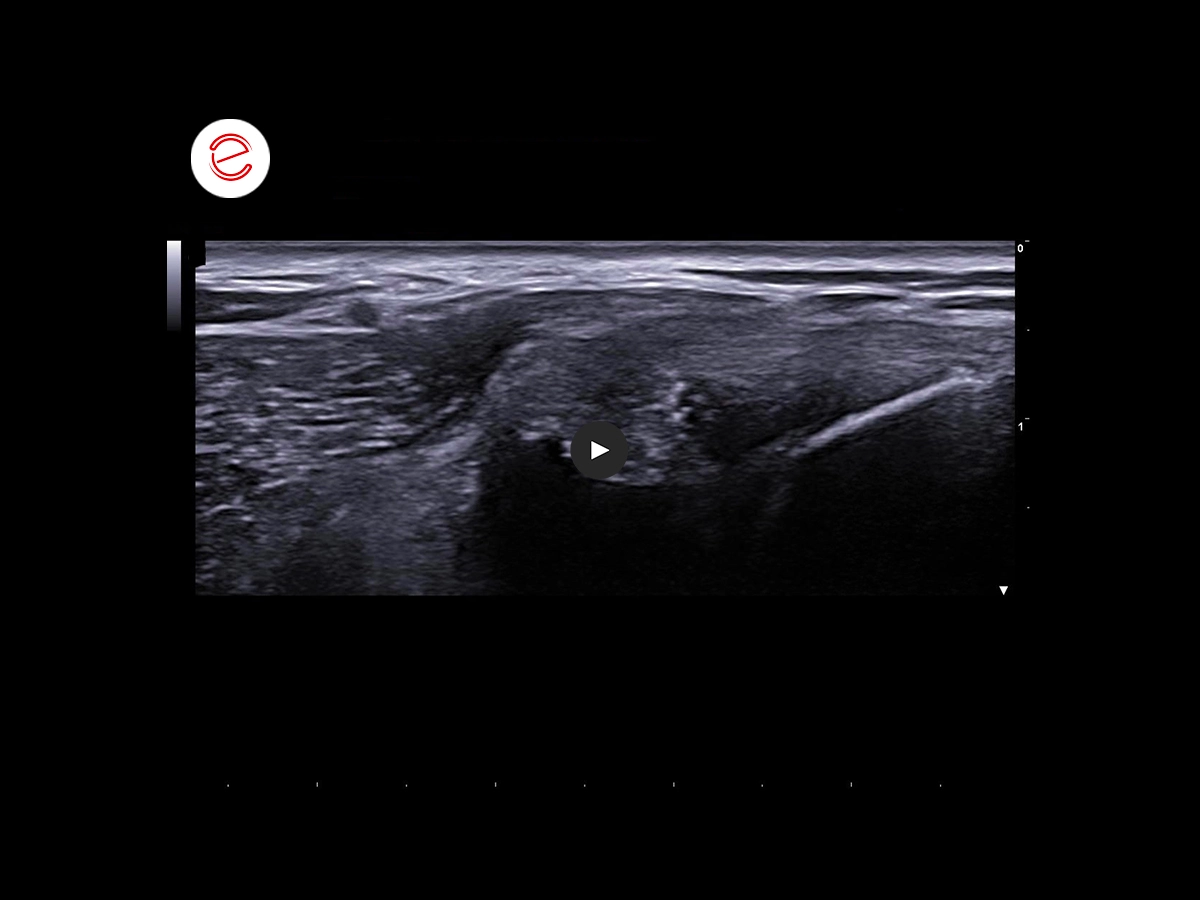

This ultrasound image, however, shows an increased volume of the left infraspinatus muscle . It appears contracted and has a hyperechogenic, globular appearance with unrecognisable echotexture.